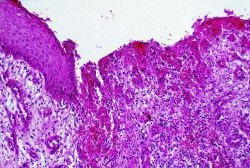

В данной статье будет подробно разбираться вопрос, как выгладит сифилитический шанкр и каковы его особенности. Также можно будет узнать, как лечить данную инфекцию. И, конечно же, будут приведены фото сифилитического шанкра и его проявлений